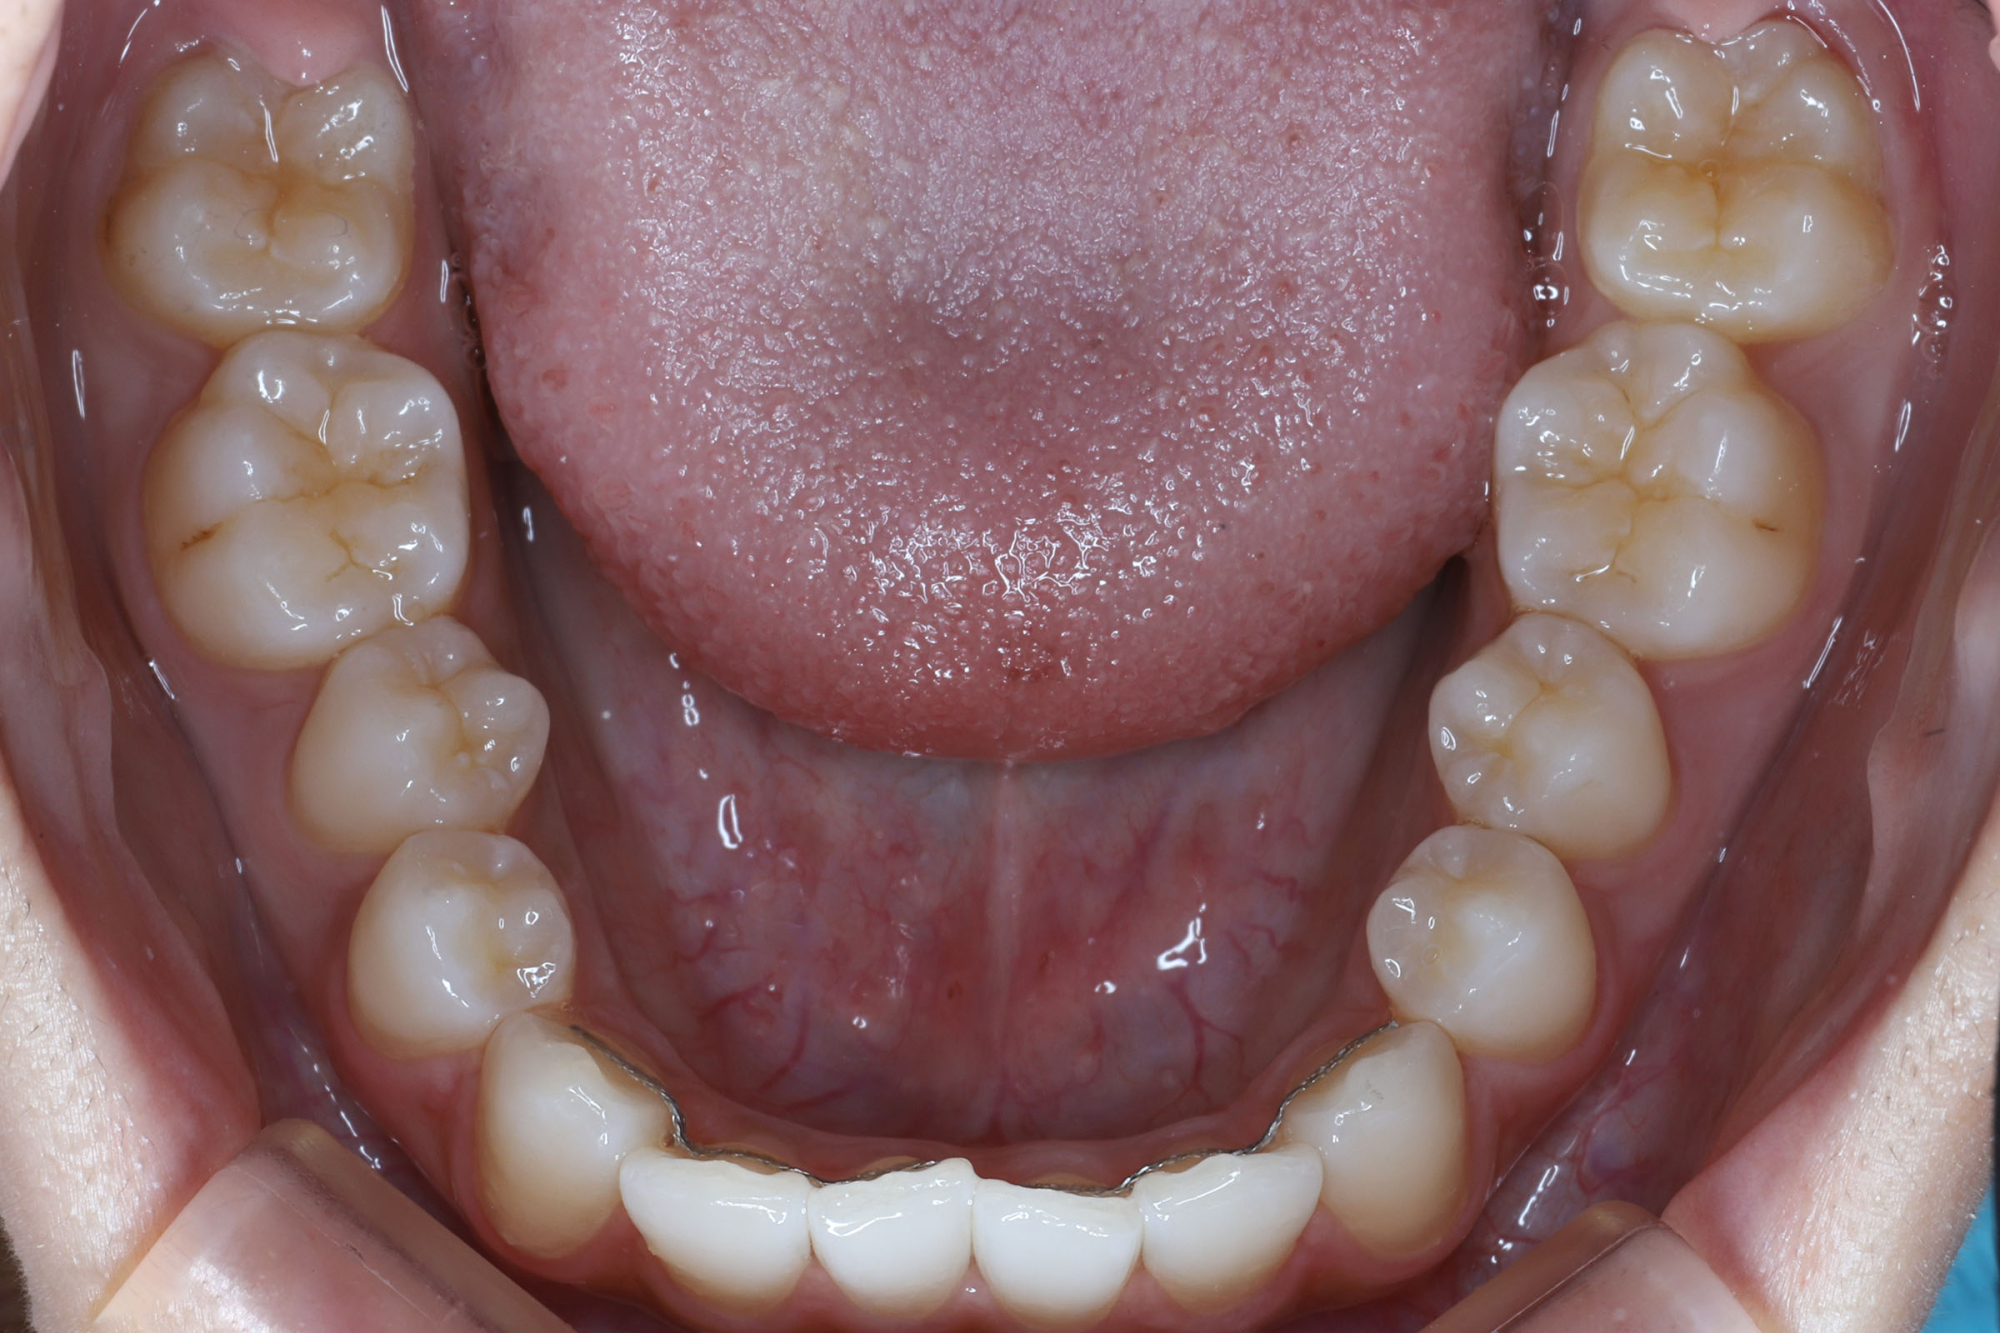

日本で行われている拡大床治療にも色々な方法がありますが当院での特長は最初に永久歯に生え替わる上下4本の前歯を奥歯の生え替わりが始まる前までに顎を拡大してきれいに並べることです。そのため拡大床治療の期間は小学校1年生頃から4、5年生頃までの間に限定しており、それまでに目的が達成できない場合には別の治療法に移行します。またゆっくりスペースを獲得するようにしているのも特長で2週間に1回ネジを回すようにしています。一般的には1週間にⅠ回ないし2回ネジを回すことが多いようです。ゆっくり進めるので一日の装着時間はお家にいるときと寝ている間だけにしています。学校や自宅以外での装着はせずゆっくり拡大していくので治療期間が長くなりますが後戻りは少なく確実になります。治療開始時期が大切ですので時期を逸した場合には拡大床治療は行いません。一般的に拡大床治療の評判が悪いのは開始時期が遅く、いつまでも治療を長引かせ治らないことによるものが多いようです。 拡大床治療はスペースを作って永久歯がならぶスペースを作ることが目標ですので細かい歯の向きや角度まで整えられないこともあります。そんな場合には別の矯正治療が必要になります。

拡大床治療で顎のスペースを拡げられるのは11歳くらいまでです。そのため個人差はありますが遅くても小学校2年生までに始めなければなりません。下の前歯が生え替わりはじめた頃から下の前歯が4本、上の前歯が2本生え替わる頃までが始め時です。すでに上下4本とも生え替わってしまった場合にはすでに遅いことが多くあります。